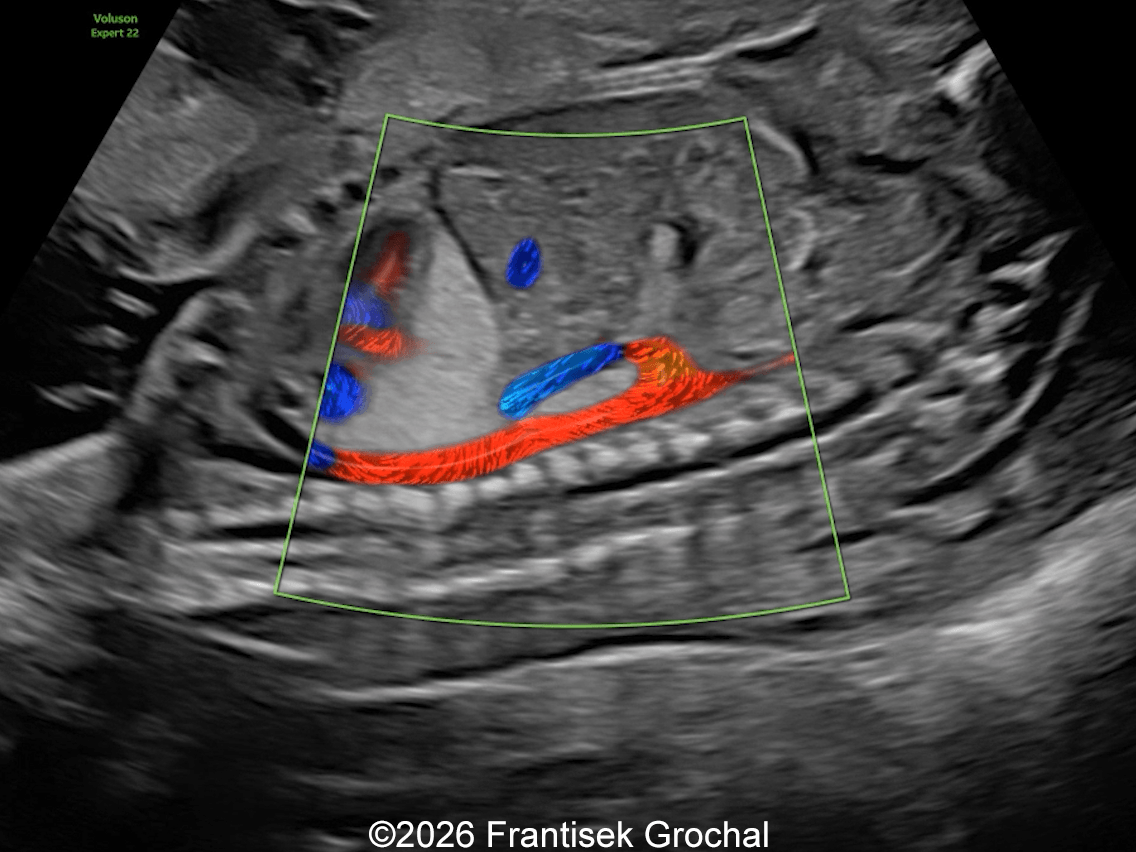

31+4 weeks – sagittal view demonstrating reduced size of the pulmonary sequestration with a small hypoechoic area within the lesion; color Doppler imaging still demonstrates a systemic feeding artery arising from the descending abdominal aorta.

Image 4 31+4 weeks – sagittal view demonstrating reduced size of the pulmonary sequestration with a small hypoechoic area within the lesion; color Doppler imaging still demonstrates a systemic feeding artery arising from the descending abdominal aorta.